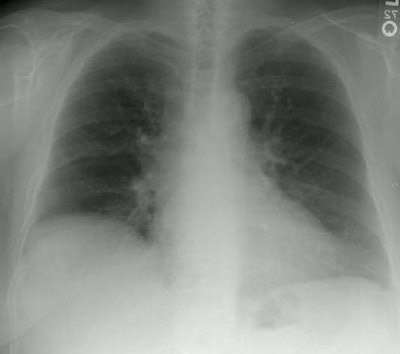

Interstitial Lung Disease in Rheumatoid Arthritis

The frontal and lateral views of the chest are from a patient with rheumatoid arthritis. The elevation of the right hemidiaphragm is a chronic finding in this patient. The films demonstrate a shaggy appearance to the heart border on the frontal examination and prominent interstitial markings are very evident over the spine on the lateral examination. See CT scan below.